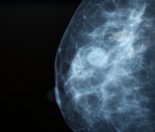

For more information on Mammograms, click here